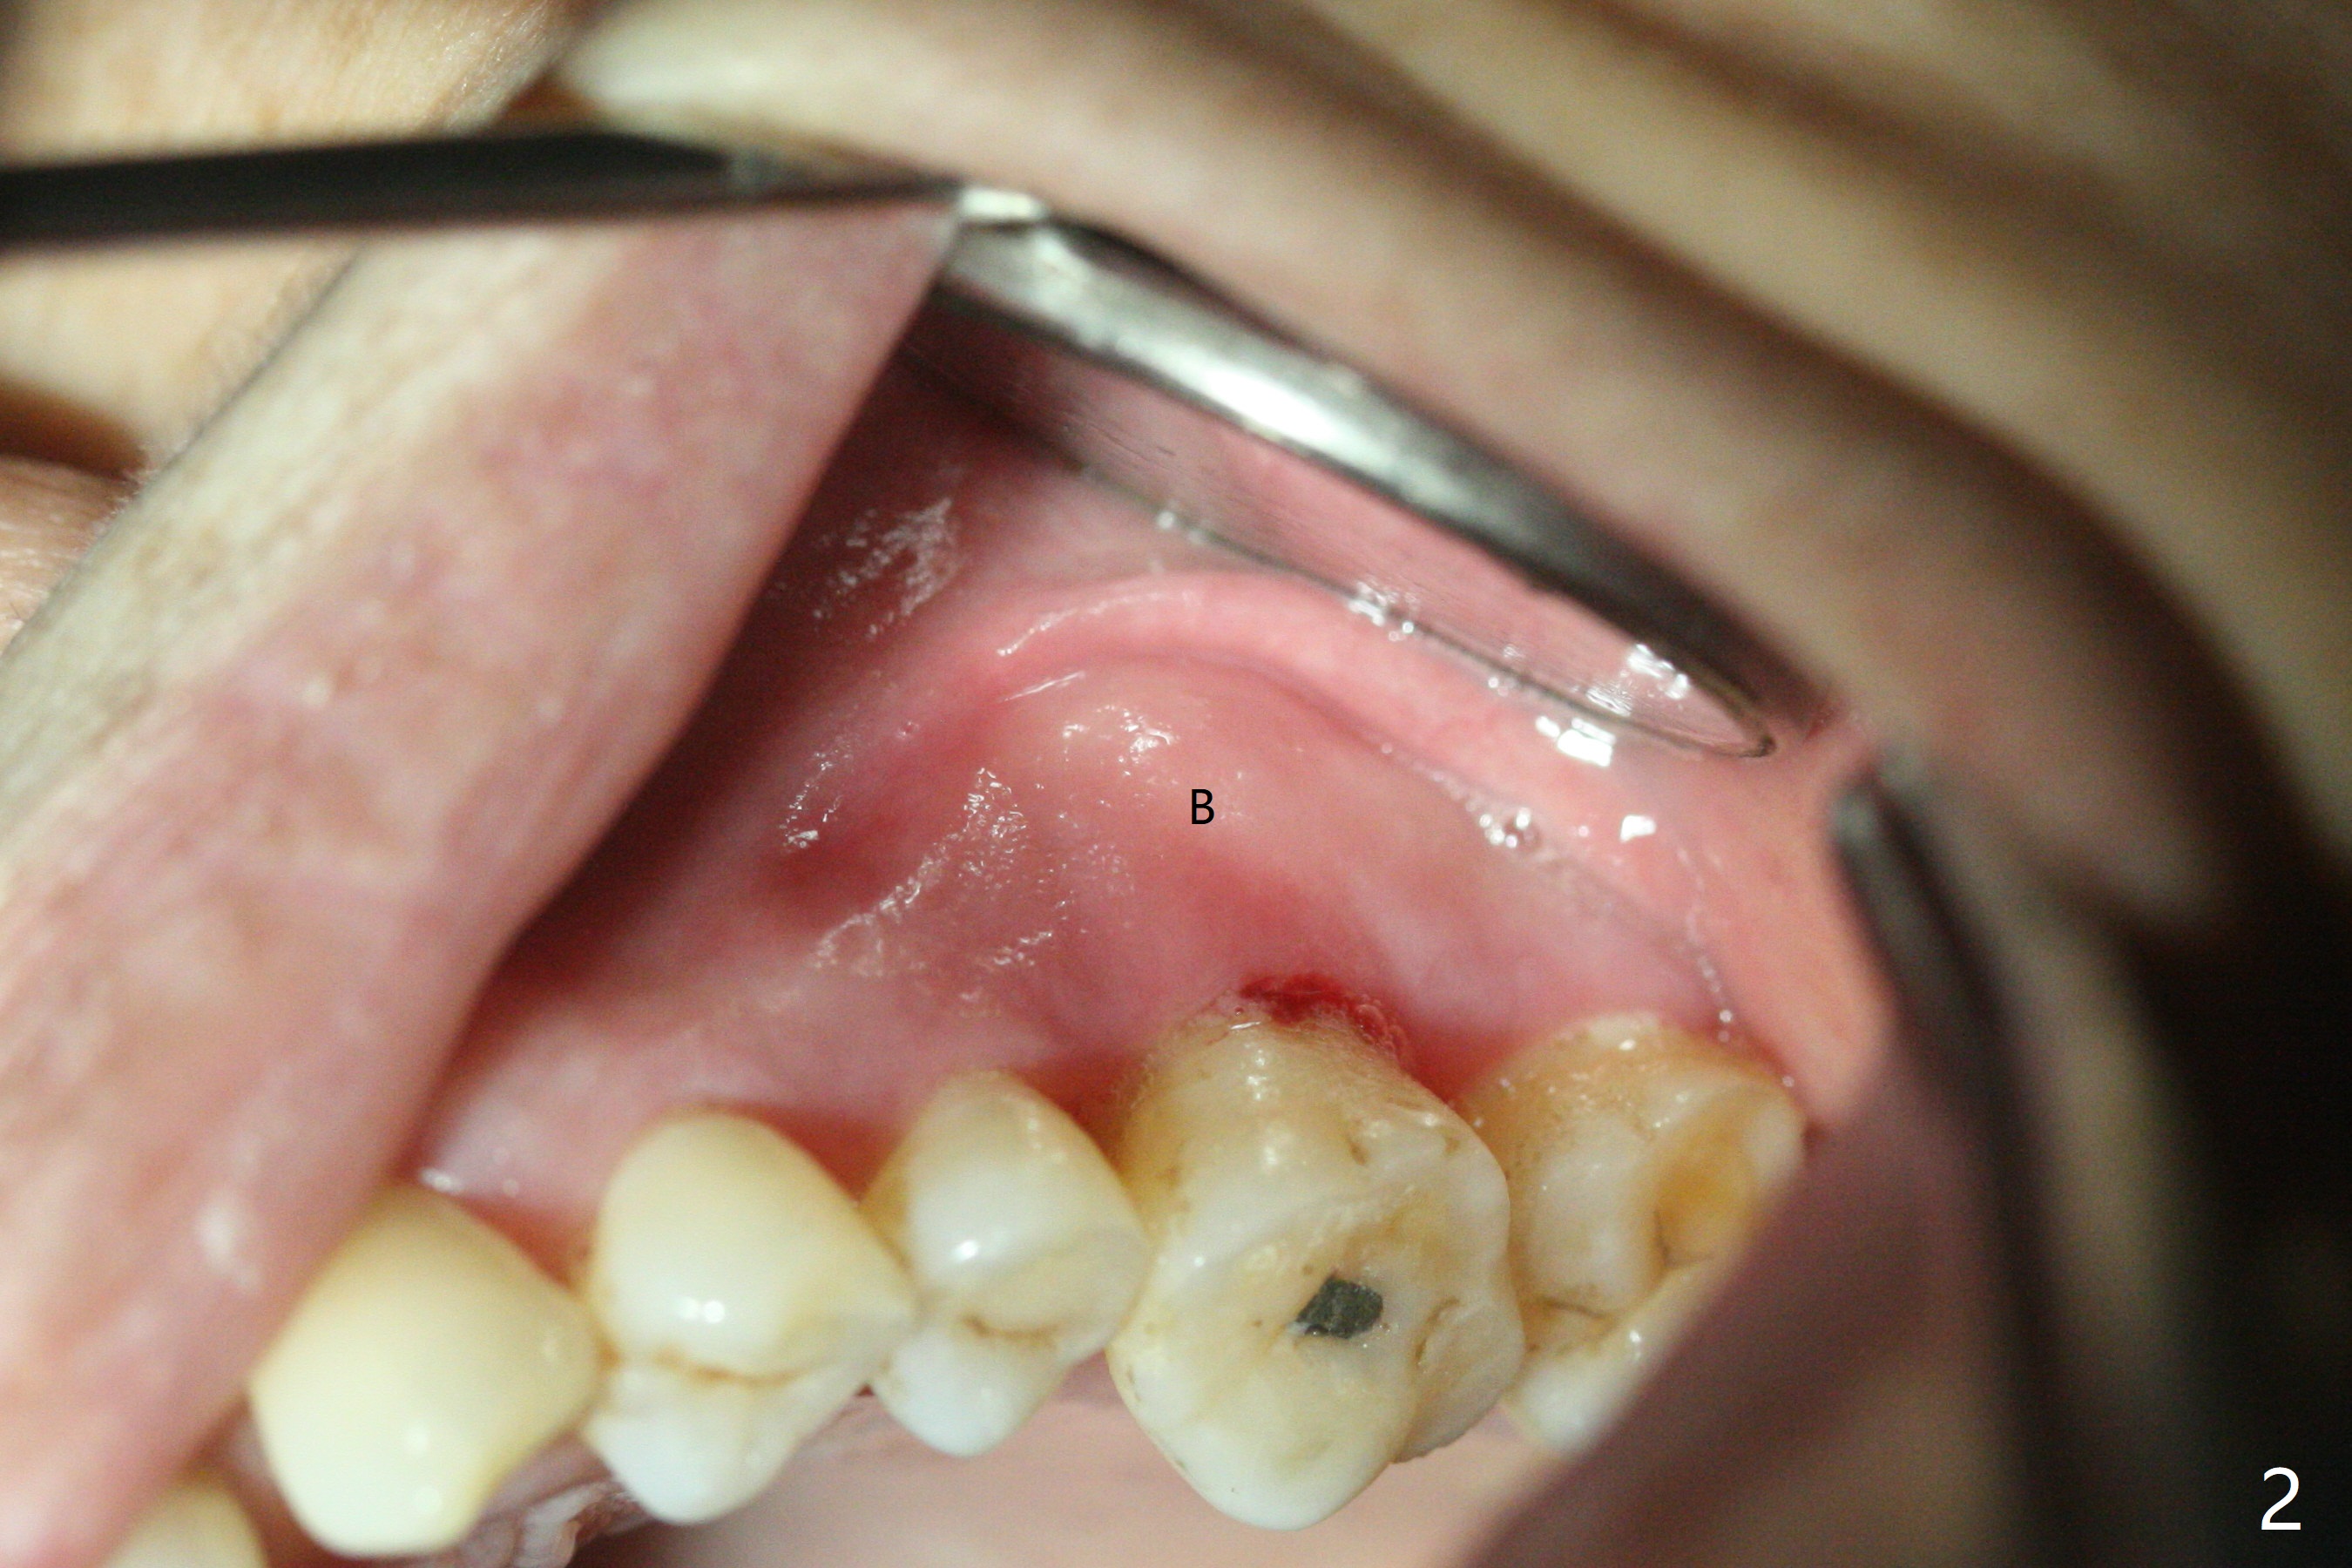

67岁女深洗后突然回来要求拔除左上六(图一),颊侧红肿,流脓,牙周袋深(图二B),经过多番劝导,终于图一植骨,由于时间仓促,使用合成血小板生长因子(GEM21S,而不是PRF))与皮质骨(125μm – 850μm)以及皮松质骨(500μm – 1,000μm)调拌,放置于巨大吸收融合颊侧牙槽窝(图三*(无颊侧骨板)(使用condenser)),而腭侧牙槽窝没有明显破坏(图一P),放置Osteogen Plug(一种骨胶原, 图三 O)。牙槽窝口放置胎盘膜(BioXclude),使用4/0 PGA缝线。傍晚病人已经 没有肿痛了。术后十三天牙周敷料脱落,伤口愈合良好。三天后病人又回来复诊(图四),折线后,虽然伤口愈合,骨粉好像填的不够多(图五),或者丢失。树脂敷料可能取得更好的结果。